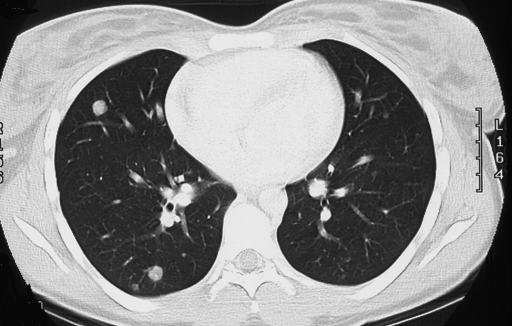

КТ ОГК. Множественные мягкотканные очаги в обоих легких у пациента с первичным раком предстательной железы